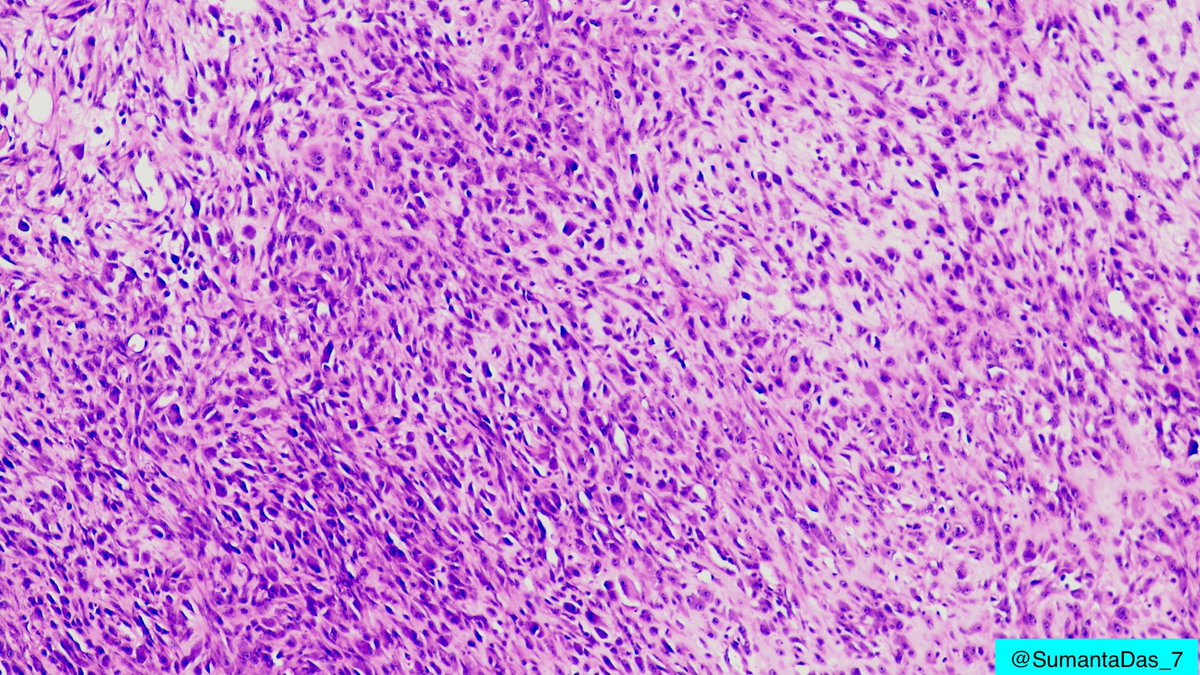

Male in 40s. Forearm mass. On low magnification, hypercellular area and hypocellular loose myxoid areas. On high magnification, sheets of ganglion-like cells with amphophilic cytoplasm, vesicular nuclei and prominent nucleoli. #PathTwitter #BSTpath